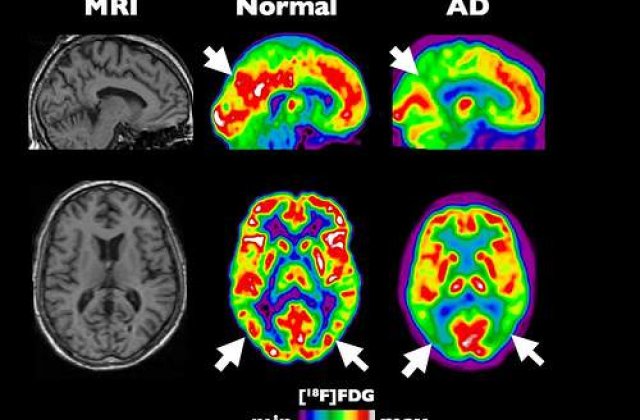

Alzheimer este o maladie cognitiva degenerativa care ataca progresiv creierul, cauzand pierderi de memorie, stare de confuzie si schimbari bruste de dispozitie. Pacientii aflati in stadiul final al bolii isi pierd capacitatea de vorbi, de a inghiti si de a se deplasa.